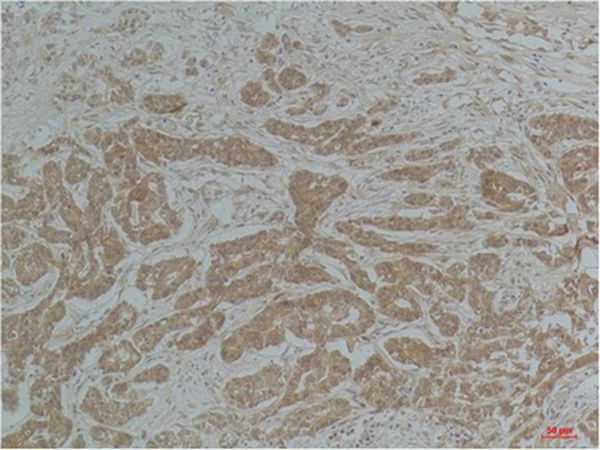

分类: 科研抗体货号: P43828别名: Cellular tumor antigen p53 (Antigen NY-CO-13) (Phosphoprotein p53) (Tumor suppressor p53)应用: IHC反应种属: Human,Mouse,Rat